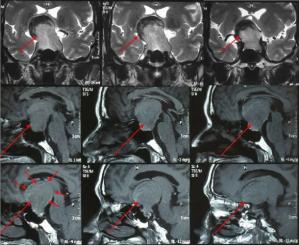

李先生4年多前就开始视力下降,曾在外院检查未作磁共振检查,未能发现病因,未引起重视。

直到车祸后头颅ct偶然发现该肿瘤,此时视力已经严重下降。

磁共振检查证实为鞍结节脑膜瘤,左侧视神经受压严重,术中发现已经萎缩。

肿瘤同时包绕重要的动脉血管,手术难度及风险加大,不容易切除彻底。

经过手术,肿瘤顺利全切,右眼视力好转,但左眼视力因神经长期受压萎缩严重难以恢复。